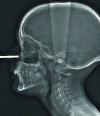

Dental radiology

Dental radiology underwent its first major evolution in the 1980s with the advent of real-time, digitized intra-oral radiology (Trophy RadioVisioGraphy ® ). This was followed by the more ergonomic ERLM (radioluminescent memory display), which provided an image in slightly delayed time, and gradually gained acceptance. It is only very recently, long after the transition from silver to digital, that 3D imaging has contributed to a major evolution in dental radiology practice, calling into question many indications. International literature and recommendations now recognize Cone Beam CT not just as an alternative to X-ray CT, but as a reference technique, registered in the nomenclature, for cross-sectional imaging in dentistry. Image quality, advantageous dosimetry and easy access have led to a gradual extension of traditional indications (oral...